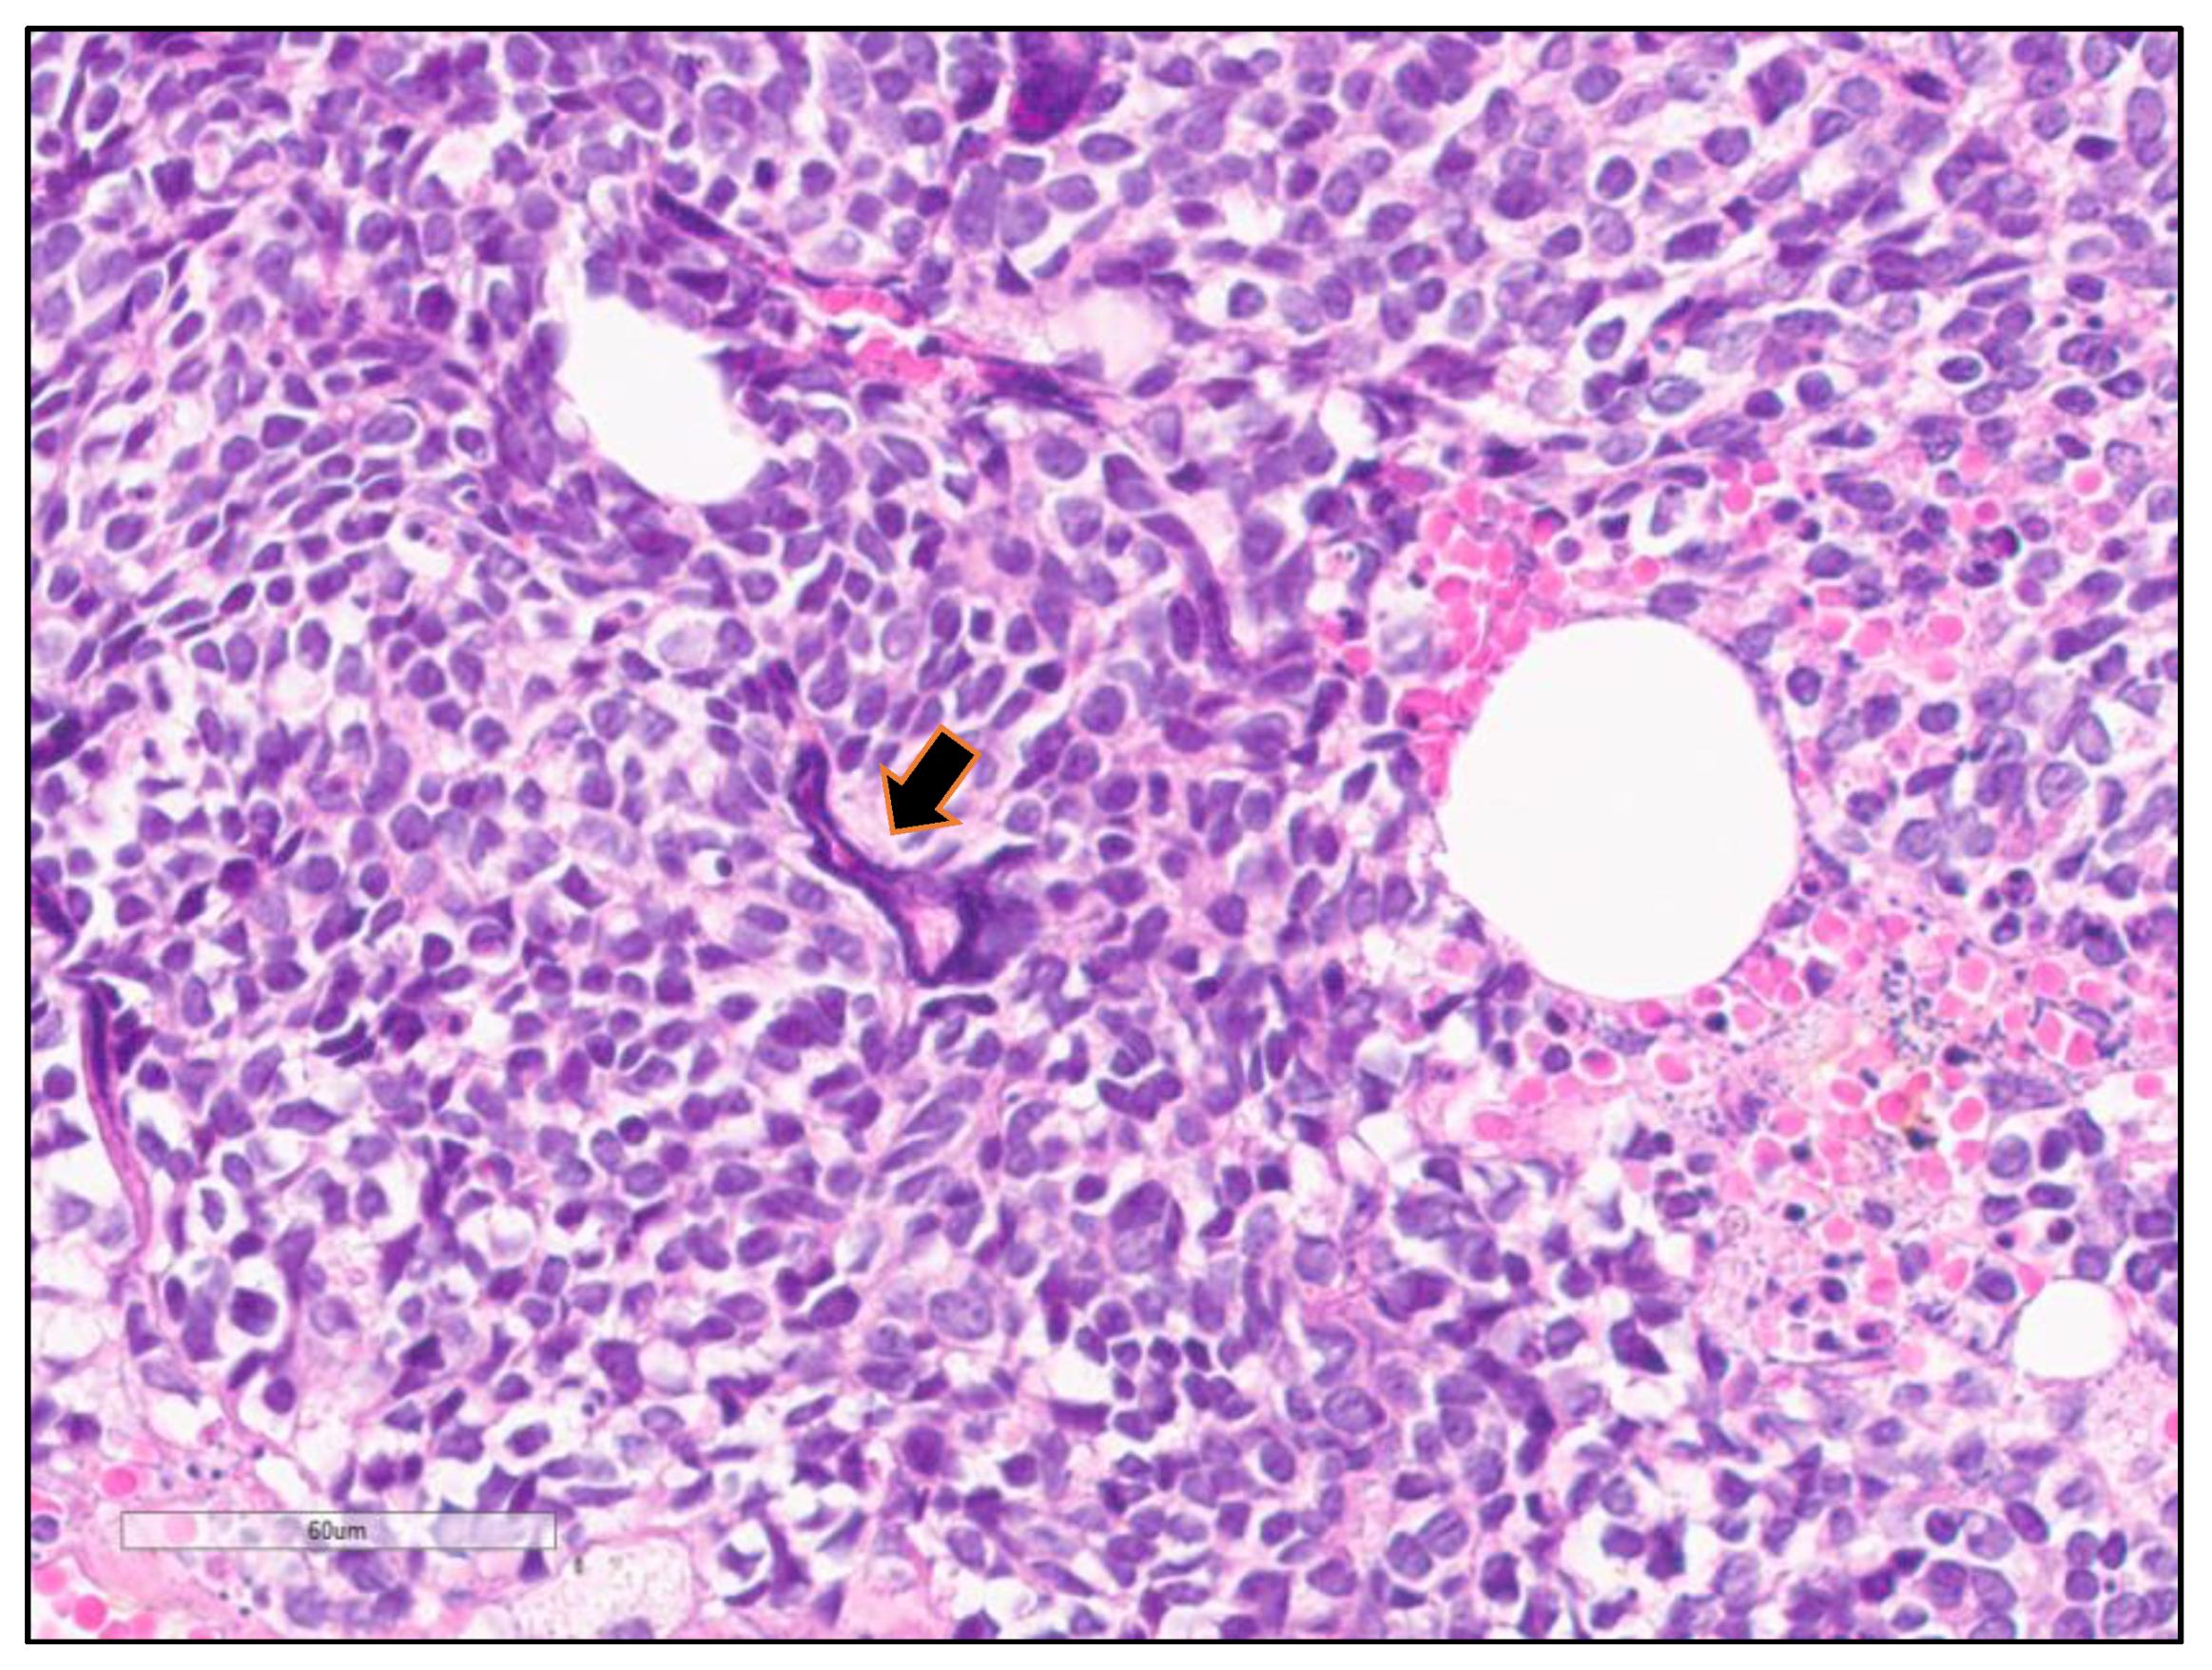

4. Microscopic Features of SCLC

4.2. Histopathological Features